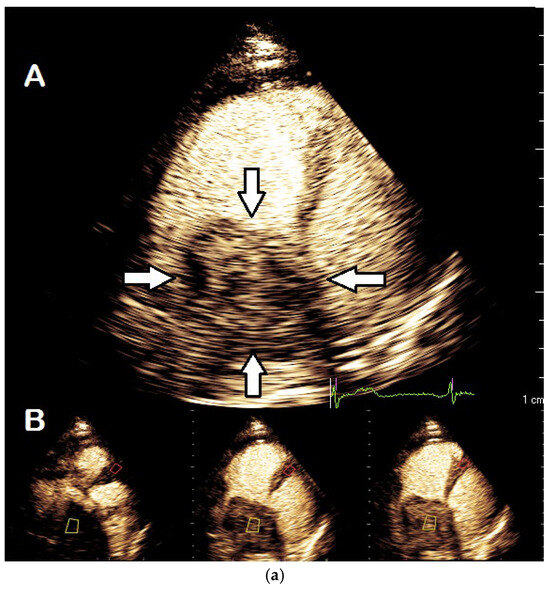

| Imaging method | start with low-MI-contrast-specific imaging for assessment of global and regional LV function then use intermediate-MI-contrast-specific imaging which provides better display of LV trabeculations |

| Imaging planes | standard apical views parasternal and apical short-axis view |

| Contrast application | bolus injection |

| Typical findings | trabeculated layer apical, lateral, and inferior: more than 3 trabeculations, ratio of trabeculated/compact myocardium >2 The number of trabeculations and the ratio of trabeculated/compact myocardium does not seem to impact clinical management |

| Alternative imaging | MRI for tissue characterization in dilated cardiomyopathy and risk assessment in hypertrophic cardiomyopathy, assessment of LV thrombi when CEUS recordings are non-diagnostic |